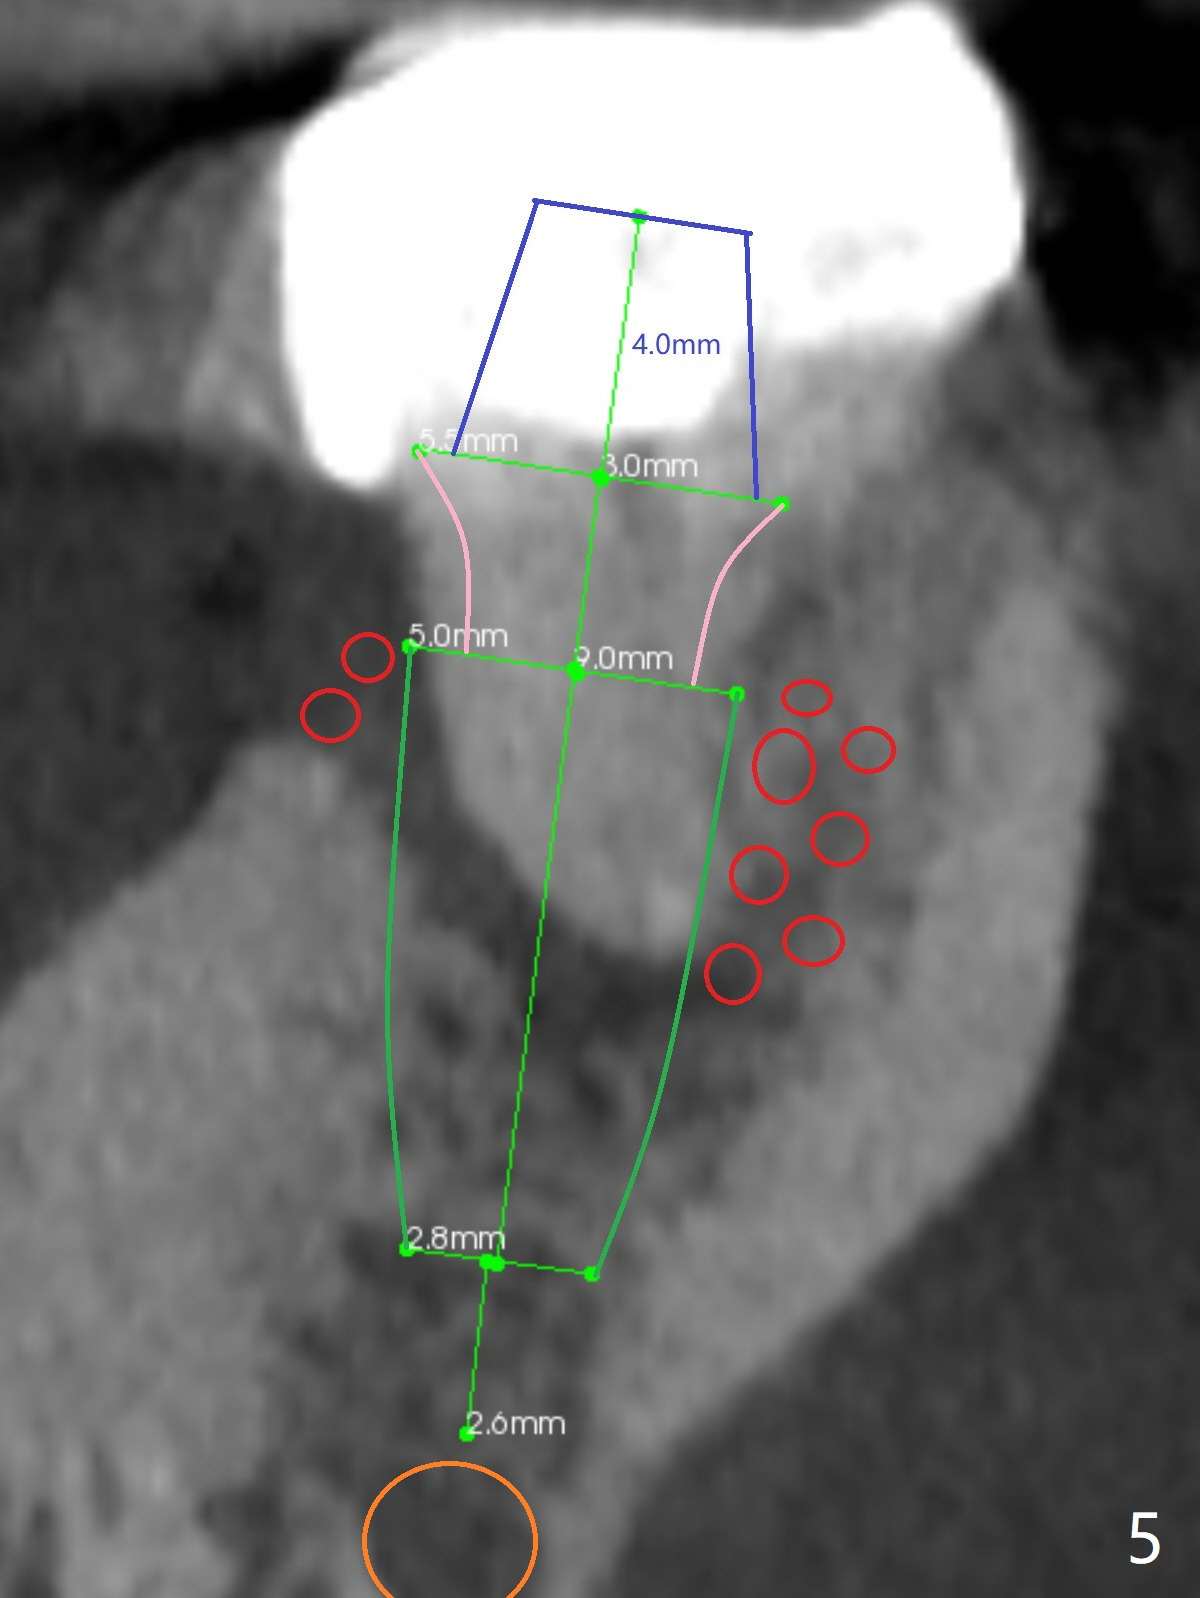

A 53-year-old man will return for #18 extraction and implant because of endo failure after the same treatment at #14 (Fig.1). It appears that the mesiolingual canal is missing for RCT (Fig.2 (coronal section at the mesial root)). Bony defect is buccodistal; try to place an implant as mesiolingual as possible (Fig.3 (axial section)). To reduce lingual (L) plate perforation and neuropathy (orange), the implant is expected to be 5-6x9 mm (Fig.4,5). Use 4 mm stopper from DIO Sinus Kit for osteotomy (Fig.1,4,5). If his vein is prominent, prepare PRF 1-2 tubes.